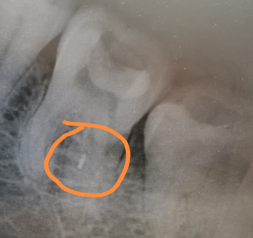

远舌根管发生器械分离

治疗术后